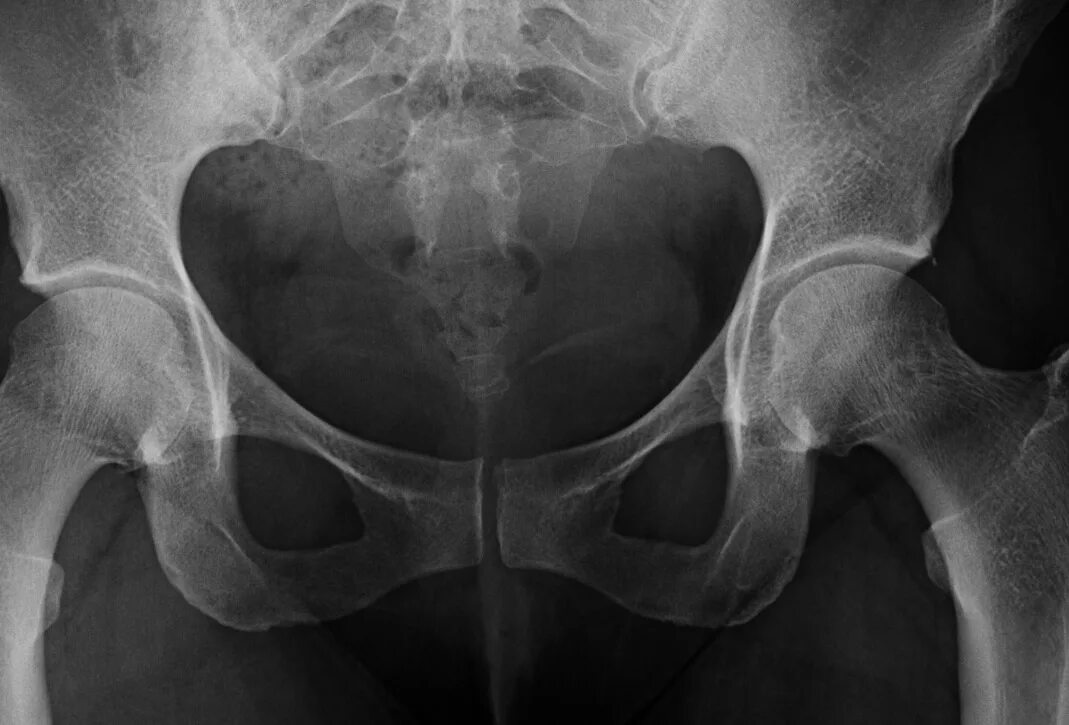

Source x rays